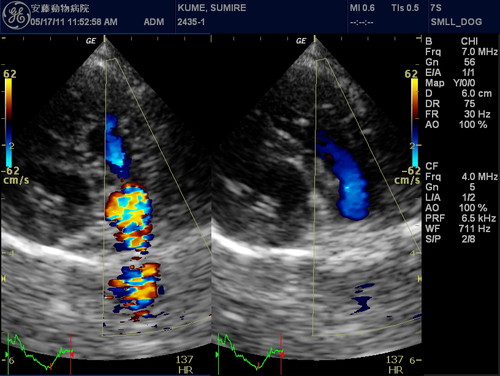

安藤動物病院では、動物の心臓病の進行状態や原因を見つけるための「確定診断サービス」を行っております。

一般身体検査(聴診など)、血液検査、心電図検査、レントゲン検査、心臓エコー検査

エコー心臓・血管造影検査

心臓エコー検査・マイクロバブル造影法